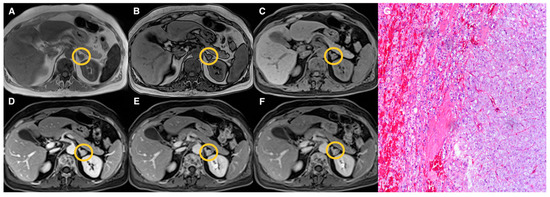

| Groups | Qualitative CS Signal Drop | Lesion Type | Total |

|---|---|---|---|

| 1 | Homogeneous | Adenomas (n = 19) | 19 |

| 2 | Heterogeneous | Adenomas (n = 17) Pheochromocytomas (n = 3) Myelolipomas (n = 3) | 23 |

| 3 | Absent | Adenomas (n = 10) Pheochromocytomas (n = 9) Primary malignant tumors (n = 5) Metastasis (n = 5) Oncocytoma (n = 1) | 30 |